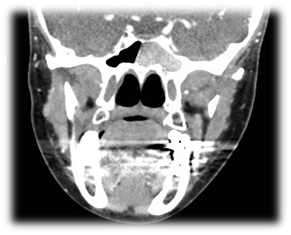

The commonest pathogens include Staphylococcus aureus, aerobic Gram-negative bacilli and anaerobes.10-14 These patients presented with headache, rhinorrhea, nasal obstruction, and blurred vision. The most common presenting symptom of sphenoid sinus disease is mainly headache. In the majority of previous reports, headache was nonspesific in location, quality and intensity.15 Physical examination and endoscopic finding may show mucopurulent secretion at the sphenoethmoidal area, edema of the sphenoethmoidal recess mucosa and polypoid tissue in the sphenoethmoidal recess. In CT scan of the sinuses (Figure 1) will show opacification in the sphenoid sinus, with mucosal wall thickening and air-fluid level. Management of these patients is medical treatment with antibiotic based on culture with topical corticosteroid and decongestant, the surgical intervention (endoscopic sphenoidotomy) (Figure 2) if failed medical treatment or patient presented with complications.

Figure 2 endoscopic sphenoidotomy for bacterial sphenoid sinusitis./p>